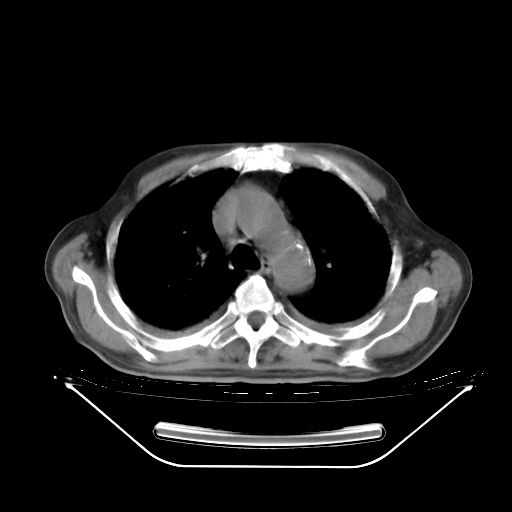

今天复查肺部CT,发现双肺广泛磨玻璃样改变。所以我把3月19日和5月9日相隔50天的肺部CT上传。请大家会诊。

2009年3月19日肺部CT片。

5月9日肺部CT(在4月27日齐鲁医院肺部CT描述部分肺组织磨玻璃样改变,12天后肺组织广泛磨玻璃样改变)